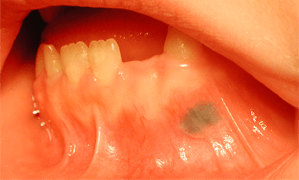

Un Rare Cas De Pigmentation De La Muqueuse Buccale Diagnostic Differentiel Et Presentation Du Cas Jcda